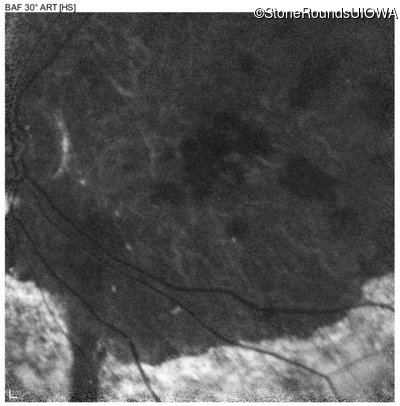

Blue Autofluorescence - Right - 20/200 sc

Exemplar

Blue Autofluorescence - Left - 20/250 sc